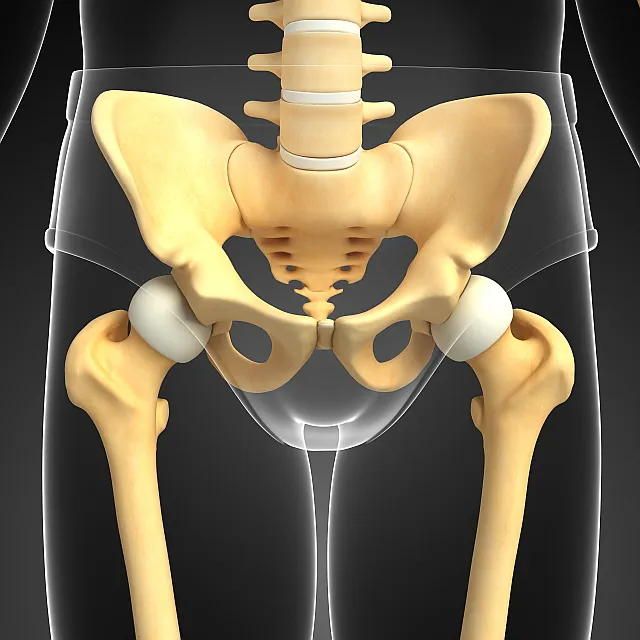

1. 고관절이란?

고관절은 골반의 관골구와 대퇴골두를 연결하는 관절입니다. 골반과 다리가 만나는 지점에 위치하며 체중을 지탱하고 다리의 움직임을 가능하게 합니다.

또한 "엉덩이 관절"이라고도 불리는 이 관절은 뼈와 뼈가 연결되어 자유로운 움직임을 가능하게 하는 신체 부위로, 허벅지와 종아리를 포함한 다리 전체를 움직일 수 있도록 돕습니다. 고관절의 움직임과 기능은 걷기, 달리기, 앉기 등과 밀접하게 연관되어 우리 몸의 움직임과 일상 활동에 핵심적인 역할을 수행합니다.